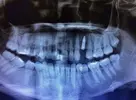

Implant Treatment